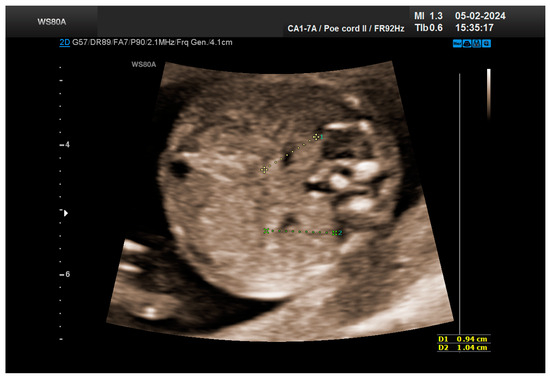

The combined test result indicated a low risk for trisomies, preeclampsia, and intrauterine growth restriction. However, during the ultrasound examination, the absence of the right renal tissue in the right parasagittal sections was noted (Figure 1). Examination of the embryo in axial sections demonstrated the presence of a relatively well-defined acoustically heterogeneous echogenic mass situated anterior to the spine, in sonographic contact with the renal tissue image correctly occupying the left lumbar fossa (Figure 2). Those aspects suggested the existence of a renal anomaly of crossed fused renal ectopia. No other embryonic anomalies were detected, the bladder image was present, and the amniotic fluid volume was normal. The calculated gestational age corresponded to the ultrasound estimate. The suspicion of crossed fused renal ectopia was maintained during a subsequent reevaluation at 17 weeks of pregnancy (Figure 3 and Figure 4).

Figure 1. Empty right renal fossa (circled in red)—first-trimester morphology scan at 13 weeks and 2 days.